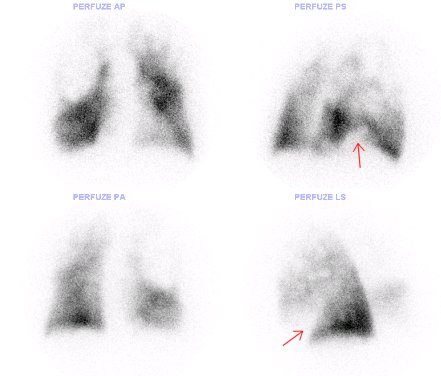

Klínovité defekty perfuse vpravo laterobazálně a vlevo vemtrolaterobazálně jsou v rámci embolizace do arteria pulmonalis – dle CT v pravé větvi plicnice nástěnný trmbus o šířce ai 15 mm a délce cca 55 mm. Vlevo patrný trombus ve větvi pro dolní lalok.

Obr. č. 1: Perfuzní scintigrafie plic – šipkou označeny defekty perfuze v rámci TEN ad pulm.